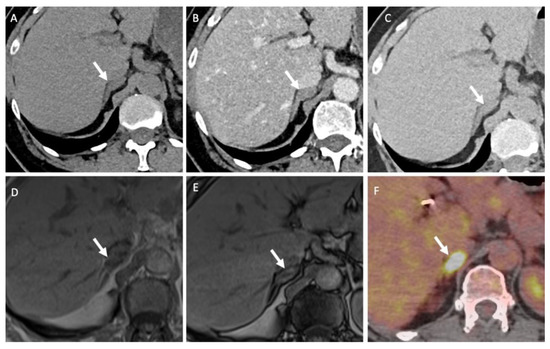

- Seo, J.M.; Park, B.K.; Park, S.Y.; Kim, C.K. Characterization of lipid-poor adrenal adenoma: Chemical-shift MRI and washout CT. Am. J. Roentgenol. 2014, 202, 1043–1050. [Google Scholar] [CrossRef]

- Haider, M.A.; Ghai, S.; Jhaveri, K.; Lockwood, G. Chemical shift MR imaging of hyperattenuating (>10 HU) adrenal masses: Does it still have a role? Radiology 2004, 231, 711–716. [Google Scholar] [CrossRef]

- Dixon, W.T. Simple proton spectroscopic imaging. Radiology 1984, 153, 189–194. [Google Scholar] [CrossRef]

- Platzek, I.; Sieron, D.; Plodeck, V.; Borkowetz, A.; Laniado, M.; Hoffmann, R.T. Chemical shift imaging for evaluation of adrenal masses: A systematic review and meta-analysis. Eur. Radiol. 2019, 29, 806–817. [Google Scholar] [CrossRef]

- Stanzione, A.; Verde, F.; Galatola, R.; Romeo, V.; Liuzzi, R.; Mainenti, P.P.; Aprea, G.; Klain, M.; Guadagno, E.; Del Basso De Caro, M.; et al. Qualitative Heterogeneous Signal Drop on Chemical Shift (CS) MR Imaging: Correlative Quantitative Analysis between CS Signal Intensity Index and Contrast Washout Parameters Using T1-Weighted Sequences. Tomography 2021, 7, 961–971. [Google Scholar] [CrossRef]

- Romeo, V.; Maurea, S.; Guarino, S.; Mainenti, P.P.; Liuzzi, R.; Petretta, M.; Cozzolino, I.; Klain, M.; Brunetti, A. The role of dynamic post-contrast T1-w MRI sequence to characterize lipid-rich and lipid-poor adrenal adenomas in comparison to non-adenoma lesions: Preliminary results. Abdom. Radiol. (NY) 2018, 43, 2119–2129. [Google Scholar] [CrossRef] [PubMed]

- Miller, F.H.; Wang, Y.; McCarthy, R.J.; Yaghmai, V.; Merrick, L.; Larson, A.; Berggruen, S.; Casalino, D.D.; Nikolaidis, P. Utility of diffusion-weighted MRI in characterization of adrenal lesions. Am. J. Roentgenol. 2010, 194, W179–W185. [Google Scholar] [CrossRef] [PubMed]

- Halefoglu, A.M.; Altun, I.; Disli, C.; Ulusay, S.M.; Ozel, B.D.; Basak, M. A prospective study on the utility of diffusion-weighted and quantitative chemical-shift magnetic resonance imaging in the distinction of adrenal adenomas and metastases. J. Comput. Assist. Tomogr. 2012, 36, 367–374. [Google Scholar] [CrossRef]